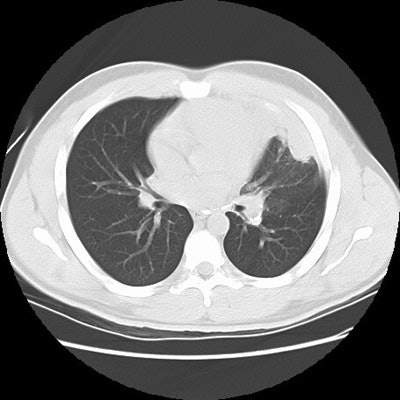

Rounded atelectasis in a patient with prior granulomatous infection

Asbestos related pleural disease is not the only cause of rounded atelectasis. The patient shown in the images below had a prior granulomatous infection with densely calcified left hilar adenopathy. There is extensive plerual thickening seen along the left anterior pleural surface. Rounded consolidated lung can be seen to abut this area of pleural thickening. Lung markings "swirl" into the area of abnormality. There is shift of the mediastinal structures to the left consistent with volume loss.